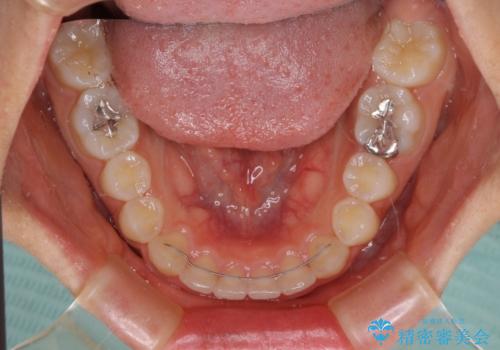

前歯のデコボコと突出感 インビザラインによる矯正治療

- 上下前歯のデコボコと、上顎前歯の突出感を気にして来院された患者様です。

インビザラインによる上下歯列の側方拡大と後方移動、IPR(歯と歯の間を削る)にるスペースの獲得により歯列を整えることとしました。

毎日22時間以上しっかりとマウスピースを装着していただいたので、スムーズに治療が進みました。歯と歯の間を削ることでうまくスペースコントロールでき、1年強で終えることができました。